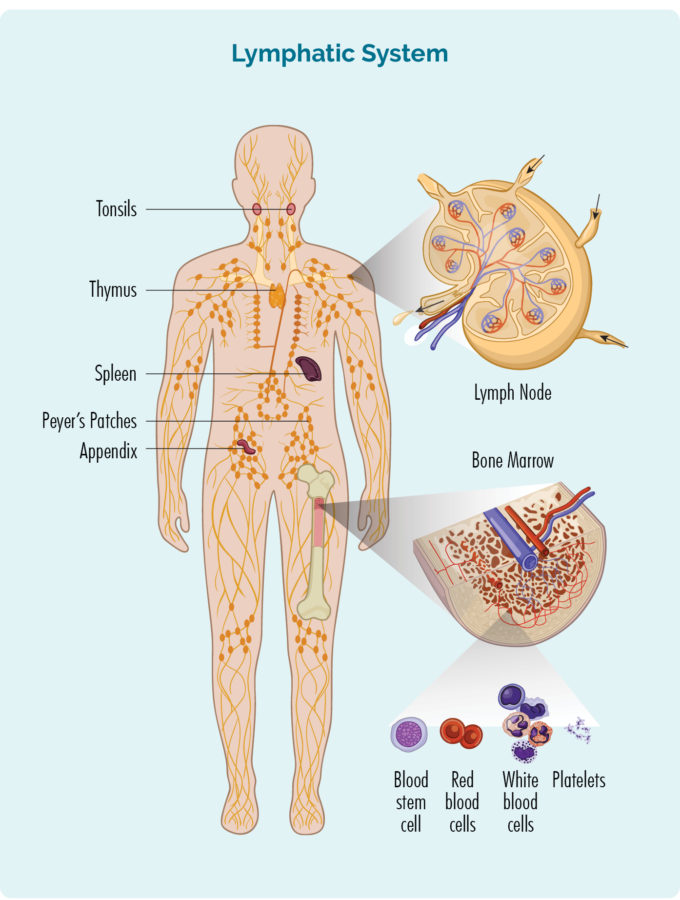

As time passed, the symptoms worsened. Travis began struggling to breathe, and his neck and jugular vein swelled. This led to a CT scan that finally revealed “multiple swollen lymph nodes.” An urgent follow-up CT scan with contrast on his chest prompted a call within 1.25 hours, instructing him to return to his GP immediately and to bring his mother. “I had never thought there was anything wrong with my chest,” he admits, despite some minor tenderness around the collarbone.

The following day, 22nd May 2025, Travis and his mother met with his GP. It was then that he learned about the mass growing in his chest: “It was explained that it was indicative and highly probable to be Lymphoma or some other form of cancer.” That same day, Travis was supported and triaged through the emergency department at Box Hill Hospital and the following day admitted into the cancer ward where a biopsy confirmed Classical Hodgkin Lymphoma Stage 2b. Travis remained at the ward for 2 weeks. The size of his ‘bulky disease’ was 14cm x 8cm x 6cm.

Before his diagnosis, Travis’s symptoms were both disruptive and puzzling. “It started with severe shoulder blade pain on my right-hand side, then neck pain, jaw pain, headaches and back pain,” he recalls. “Eventually it progressed into nerve pain down my right arm and the inability to sleep, causing fatigue.” Despite seeing multiple specialists, undergoing scans, and trying various medications, nothing seemed to help. Over time, the pain worsened, and new symptoms appeared, shortness of breath, swelling around his jugular vein, and neck swelling.